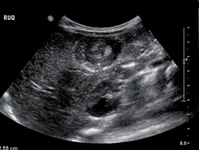

Sonograma transversal do abdome mostrando o sinal de rosca (anéis concêntricos dentro do lúmen de uma alça distendida do intestino)

Adaptado do Student BMJ. 2008;16:76. Copyright 2010 pelo BMJ Publishing Group; usado com permissão